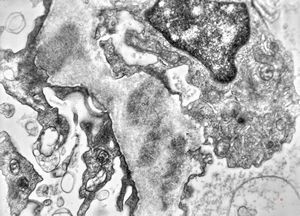

M,17y. | Alport syndrome - split and laminated basement membranes